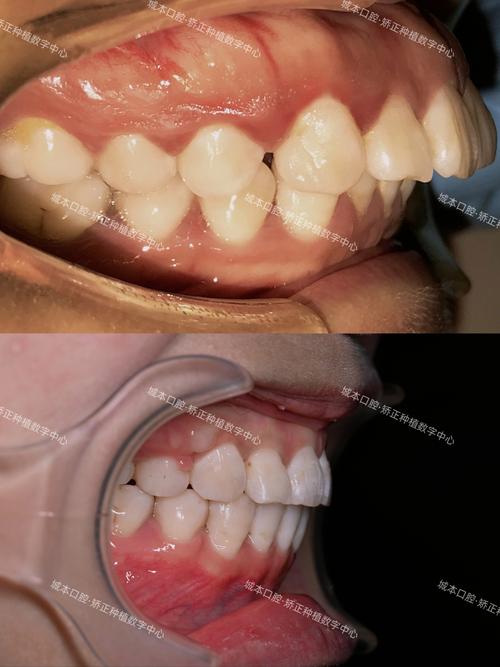

牙齿矫正是通过外力引导牙齿在牙槽骨内移动,最终达到排列整齐、咬合协调的目的,而这一过程的核心基础是牙槽骨的改建能力,牙槽骨作为包围和支持牙齿的颌骨组织,具有高度的代谢活性,在牙齿移动过程中会不断发生“吸收与重建”——受压侧的牙槽骨被破骨细胞吸收,牵引侧则由成骨细胞形成新骨,这种动态平衡是矫正成功的生理保障,部分患者在矫正过程中或矫正后可能出现“牙槽骨增生”现象,这一概念既包含正常的生理性改建,也可能涉及病理性变化,需结合具体情况分析。

牙槽骨增生本质上是骨组织对机械力刺激的响应,其核心是成骨细胞与破骨细胞的活性平衡,在牙齿矫正中,当矫治器(如托槽、弓丝)对牙齿施加持续、轻柔的牵引力时,牙齿周围的牙周膜受到牵拉,会释放多种生长因子(如BMP、TGF-β),刺激牙槽骨内壁的成骨细胞分化增殖,在牵引侧形成新骨,使牙槽骨宽度增加、高度调整,以适应牙齿的新位置,这种增生是矫正目标实现的必要过程,通常表现为牙槽骨密度的适度升高、骨小梁排列更规则,属于“生理性增生”。

生理性牙槽骨增生通常无明显临床症状,通过影像学检查(如X光片、CBCT)可观察到牙槽骨形态逐渐规则,密度均匀升高,牙齿移动稳定,属于矫正过程中的正常现象,而病理性增生则可能带来一系列问题: